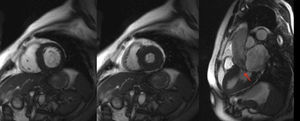

Mujer de 69 años, con síncopes y reciente diagnóstico de miocardiopatía hipertrófica, fue remitida a nuestra unidad de imagen para completar estudio con resonancia magnética cardiaca. Esta confirmó la miocardiopatía hipertrófica (septo mediobasal de 17 mm) con obstrucción al tracto de salida del ventrículo izquierdo y movimiento sistólico anterior de la válvula mitral (figura 1). En los cortes axiales anatómicos, se observó una imagen compatible con doble arco aórtico (figura 2), que se confirmó con la realización de aortografía con contraste y posterior reconstrucción tridimensional. Las imágenes tridimensionales (figura 3) mostraron un doble arco aórtico completo con origen de subclavia y carótida derechas en el arco derecho y de carótida y subclavia izquierdas en el izquierdo. La paciente negó tener síntomas que pudiesen estar en relación con este hallazgo (disfagia, estridor o disnea).